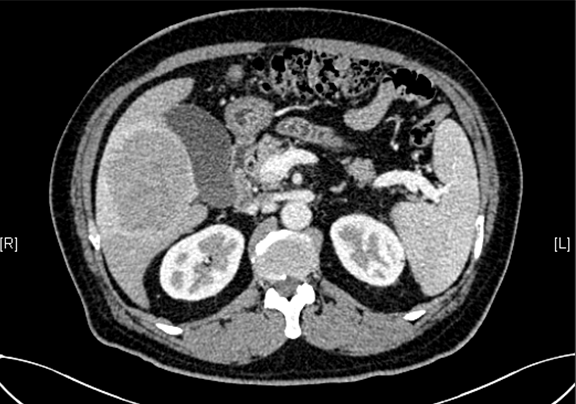

下腹部增强CT示:肝右叶恶性肿瘤可能性大;肝内多发小囊肿;肝硬化,食管胃底静脉曲张可能性大;脾脏囊肿可能性大。

术前CT检查:

动脉期

静脉期

平衡期